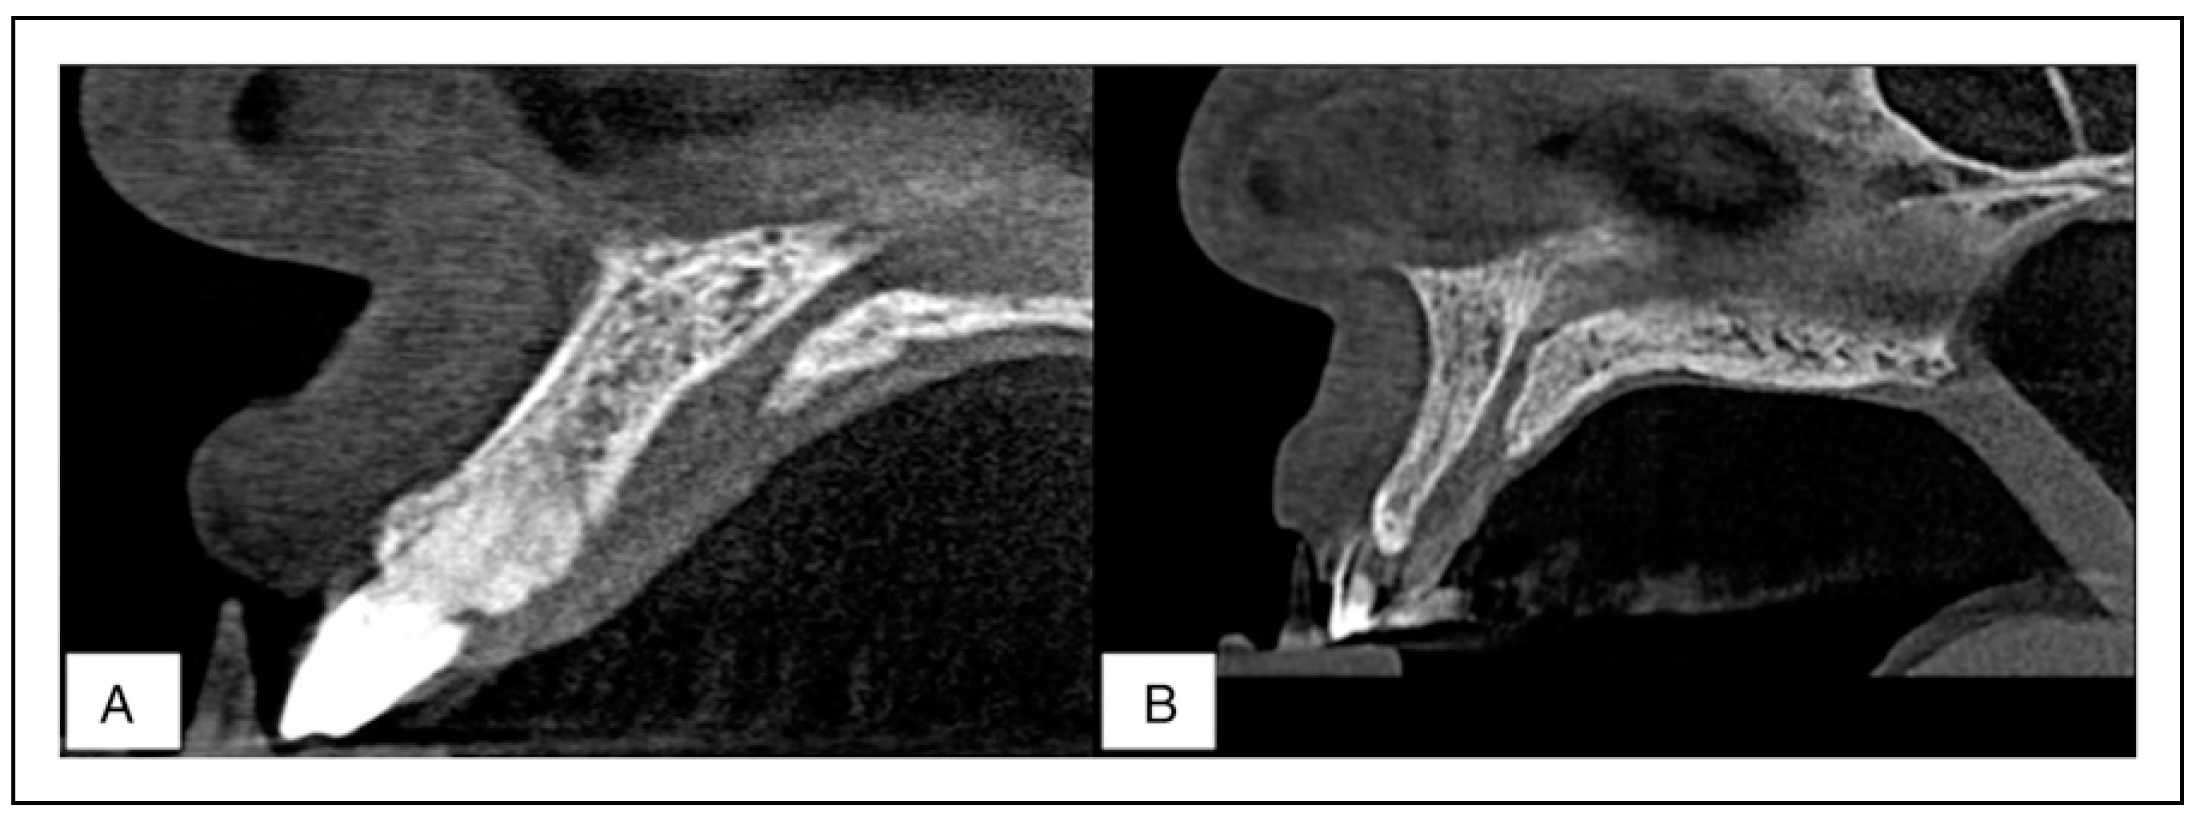

The mean length of the NPC in males was found to be 14.43 ± 3.27 mm which was significantly greater than that of the females at 11.98 ± 3.23 mm (Independent t-test, P <.05). The anteroposterior diameter of the NPC in females was greater at all 3 levels as compared to the males; conversely, the mediolateral diameter of the NPC in males was greater than that of females. These results, however, did not exhibit any sexual dimorphism (Independent t-test, P >.05). As pertains to the angulation of the NPC, the results show a similar inclination in both genders at 118° to the horizontal plane (Table 2). Two views were used in the examination of the morphology of the NPC: a sagittal view and a coronal view. In the sagittal view (Figure 3), the most common shape of the NPC for males was cylindrical followed by an hourglass, conical, banana, funnel, and tree branch patterns. On the other hand, the most common shape in females was cylindrical as well, followed by funnel, conical, banana, hourglass, and tree branch patterns. In the coronal view (Figure 4), a single canal was the most prevalent for both genders followed by the double canal for males and the Y-shaped canal for the females.

The results reveal a statistically significant difference pertaining to the shape of the NPC in both sagittal and coronal views with respect to gender (Chi-square test, P <.05).

Figure 3. Representative sagittal CBCT sections of the NPC showing the various shapes encountered in the study with, a clustered column bar chart showing the shape prevalence of the NPC in a sagittal view for both male and female Kenyans. A combined percentage value for both genders is also depicted. (a) Cylindrical (b) Hourglass (c) Conical (d) Banana (e) Funnel (f) Tree branch.